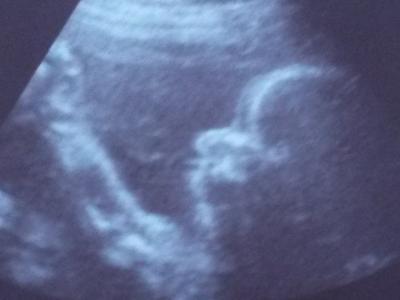

War gerade beim FA. Habe ein großes Kompliment bekommen, weil meine Werte alle so super aussehen. Beim Ultraschall hat sich der Kleine dann von seiner besten Seite gezeigt ;) denn er war nur am rum Turnen. Selbst meine FA meinte eben, dass es schwer ist ihn einzufangen. Maße passen und beim Gewicht ist er auch schon über 1000 g. Was war mein Freund eben stolz. Ende gab es dann doch noch ein Foto.

Bild zu Turnstunde beim FA - Forum für Mai - Mamis